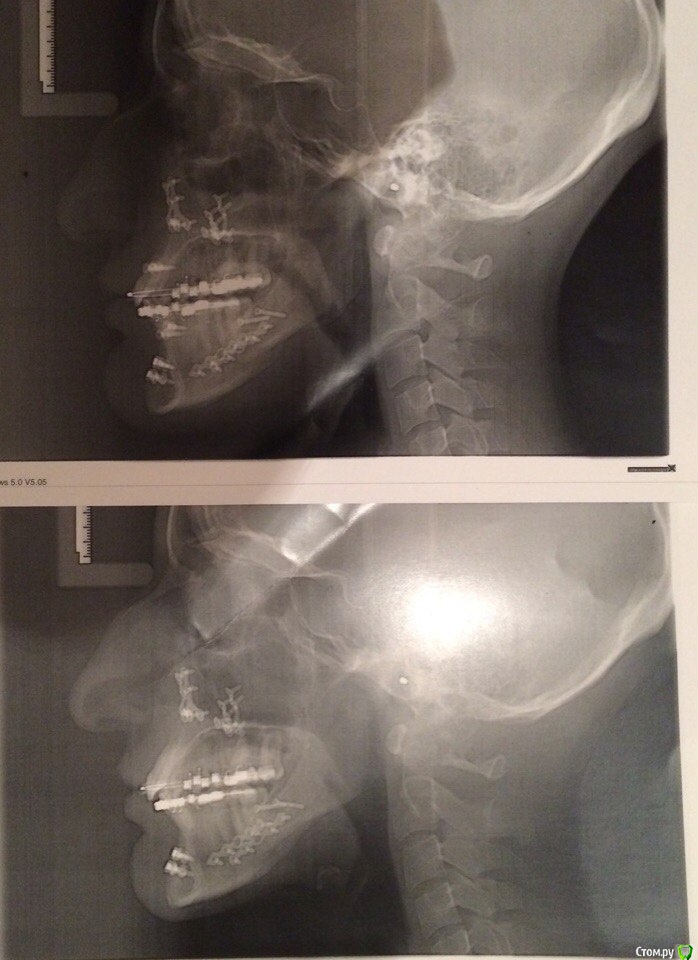

annurka Опубликовано 13 сентября, 2017 Автор Поделиться Опубликовано 13 сентября, 2017 (изменено) А До лечения есть ТРГ посмотреть? И фото какие-нибудь?есть трг сверху - сразу после остеотомии, снизу - через полгода после (когда резцы отошли друг от друга на 5мм) до лечения вообще точно делал ортодонт (снимки, слепки, фото), если в клинике это сохранили, я смогу сфотографировать. далее фото в процессе лечения - 4ки нижние еще не удалены, один хирург был готов так оперировать, другой сказал, что наклон нижних резцов неправильный и нужно как и было запланировано удалить 4ки, сепарации недостаточно.челюсть расслаблена как есть: НЧ подвинута к ВЧ для наглядности: есть фото слепков того периода, но форум ругается на слишком большой размер. если нужно - уменьшу залью) Изменено 13 сентября, 2017 пользователем annurka 1 Ссылка на комментарий

annurka Опубликовано 13 сентября, 2017 Автор Поделиться Опубликовано 13 сентября, 2017 (изменено) вот трг до начала лечения, фото к сожалению нет, если только из жизни) расшифровка трг ДО (где выделено синей ручкой) и недавнее Конечно контакты не идеальны, но если удалить 4ки наверху нижняя треть лица будет иметь довольно вогнутый вид спасибо за комментарий! а если сделать сепарацию резцов, тогда получится избежать вогнутости профиля? С ДВНЧС у вас сейчас проблемы остались? Можно рассмотреть совместно с врачом аппараты для выдвижения нижней челюсти,если тяги не справляются не было до недавнего времени - сейчас иногда болит в области сустава слева (видимо потому что контакты справа уже есть, а слева в процессе, поэтому нагрузка на челюсть неравномерная ?). до операции (но после начала лечения брекетами) сустав не беспокоил, надеюсь это просто период реабилитации.насчет аппаратов по выдвижению НЧ - спасибо, передам ортодонту.с6нимки к сожалению выполнены в разных клиниках, но мне казалось что если судить по трг через полгода, то НЧ там же, где была закреплена титановыми пластинами сразу после остеотомии (но проблема с резцами тогда уже возникла)... или мне так только кажется и произошел рецидив? думаете ее можно еще двинуть вперед? Изменено 13 сентября, 2017 пользователем annurka Ссылка на комментарий

Brigita Опубликовано 13 сентября, 2017 Поделиться Опубликовано 13 сентября, 2017 (изменено) Нет, я трг пока не могу рассчитать, чтобы это утверждать - на выходных только время будет, а пока с телефона смотрю. Предполагаю,да.Ну и плюс контакты зубы ищут правильные и смыкаются в разном положении Изменено 13 сентября, 2017 пользователем Brigita Ссылка на комментарий

annurka Опубликовано 14 сентября, 2017 Автор Поделиться Опубликовано 14 сентября, 2017 (изменено) Нет, я трг пока не могу рассчитать, чтобы это утверждать - на выходных только время будет, а пока с телефона смотрю. Предполагаю,да.Ну и плюс контакты зубы ищут правильные и смыкаются в разном положениивообще к обоим трг (до и нынешнее) я добавила расшифровку выше, или вы имеете ввиду те, что с титановыми конструкциями? мне все же хочется верить что это с зубами беда, и они новой челюсти не подходят, а не то что челюсть куда-то съехала.. в принципе, как и любому человеку, пережившему перемещение двух челюстей. еще есть такое фото, сделала его сразу после операции, швы не позволяли толком губы раскрыть, а рот нельзя было открывать на протяжении месяца, поэтому такое качество: http://i12.pixs.ru/thumbs/5/6/2/w1BZH71BWi_3410341_27523562.jpghttp://i12.pixs.ru/thumbs/5/5/3/4pJjOEAIq2_4300116_27523553.jpg там видно, что резцы сходятся как следует, а больше никаких контактов нет у других зубов. эластик (который скреплял от движения челюсть) в то же время создавал контакты клыков, носила только их месяца 4. фото через месяц после оп, тенденцию верхних резцов уже видно (но рот мне еще открывать нельзя было)http://i12.pixs.ru/thumbs/6/4/3/IMG5512JPG_8912889_27523643.jpghttp://i12.pixs.ru/thumbs/6/3/1/4pJjOEAIq2_7818185_27523631.jpghttp://i12.pixs.ru/thumbs/6/4/9/IMG5522JPG_8755357_27523649.jpghttp://i12.pixs.ru/thumbs/6/5/1/IMG5525JPG_1306296_27523651.jpg спустя 2 месяца после оп, стала жевать еду, открывать рот могла только на 2смhttp://i12.pixs.ru/thumbs/6/5/7/IMG9072JPG_6555113_27523657.jpghttp://i12.pixs.ru/thumbs/6/6/5/IMG9080JPG_2398494_27523665.jpghttp://i12.pixs.ru/thumbs/6/7/3/IMG9085JPG_1231417_27523673.jpg по ссылке доступно увеличенное изображение, спасибо Skip Изменено 14 сентября, 2017 пользователем annurka Ссылка на комментарий